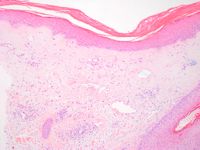

Aan het oppervlak bestaan er verstreken retelijsten en hyperkeratose. Er kan ook atrofie van de epidermis zijn (niet noodzakelijk). Er is matige vacuolisatie van het grensvlak. De dermis wordt gekenmerkt door homogenisatie van het collageen. Tevens kan er een peri-vasculair lymfocytair ontstekingsinfiltraat bestaan bij vroege lesies. Er bestaat een gehomogeniseerd stroma met teleangiectatische vaatstructuren.

Histologie van lichen sclerosus Histologie van lichen sclerosus

lichen sclerosus lichen sclerosus

Histologie lichen sclerosus Histologie lichen sclerosus

ingescande coupe (zoom) ingescande coupe (zoom)